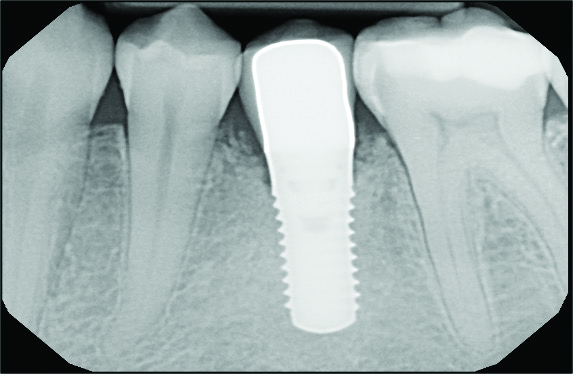

A postsurgical periapical x-ray was taken (Figure 9). Postoperative visits were at 2- to 3-week intervals. The patient was instructed to use chlorhexidine for 2 weeks, followed by the use of a two-row soft toothbrush and interproximal flossing. Interproximal proxy brush usage began after the suture removal at 4 weeks. After 2 months, healing was excellent (Figure 10); at 9 months, the interproximal papillae regeneration was complete, and radiographic confirmation of radiographic intrabony defect fill was observed (Figure 11 and Figure 12). After 1 year, maintenance visits were conducted by the restorative office's registered dental hygienist.

Six-year and 11-year recall visits (Figure 13 through Figure 15) confirmed stable long-term soft- and hard-tissue regeneration and bone healing.

Fig 11. Radiograph at 9-month follow-up showing intrabony defect fill.

Figure 11

Fig 13. Radiograph at 6-year recall.

Figure 13